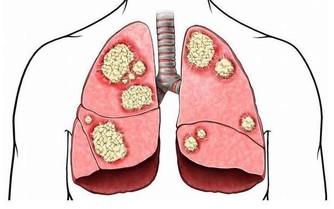

3、維生素A可抗肝癌

研究表明,維生素A能保護肝臟,阻止和抑制肝臟中癌細胞的增生。每天喝一杯牛奶就可以滿足肝臟對維生素A的需求。